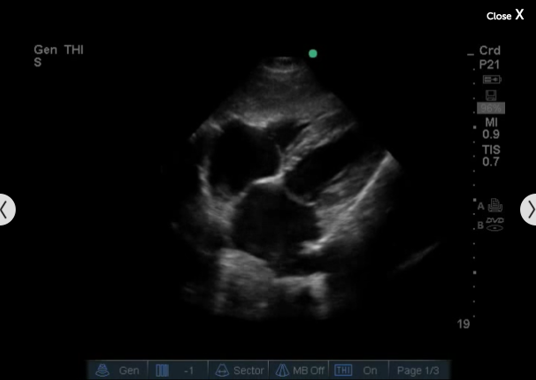

Imagen cardíaca desde el plano subxifoideo 2